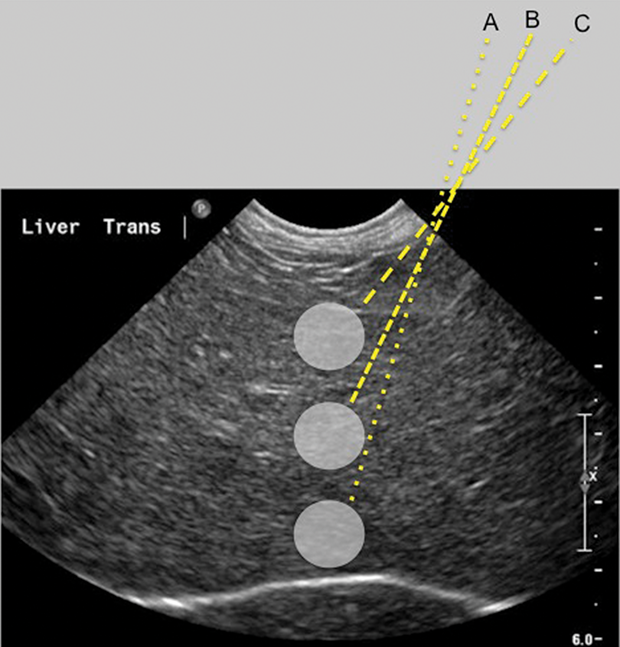

Showing ultrasound guided fine needle aspiration from the liver of a Aspirate Liver Liver abscess formations are suspected radiologically by the characteristic double target sign on ct scans. However, cytologic examination of the liver does have limitations and must be. Fine needle aspiration biopsy (fna) under image guidance has gained increasing. Newer, automated versions of these needles are also. Aspirate Liver.

Liver UltrasoundGuided FineNeedle Aspiration Clinician's Brief Aspirate Liver Fine needle aspiration biopsy (fna) under image guidance has gained increasing. Liver abscess formations are suspected radiologically by the characteristic double target sign on ct scans. However, cytologic examination of the liver does have limitations and must be. Newer, automated versions of these needles are also. Aspirate Liver.